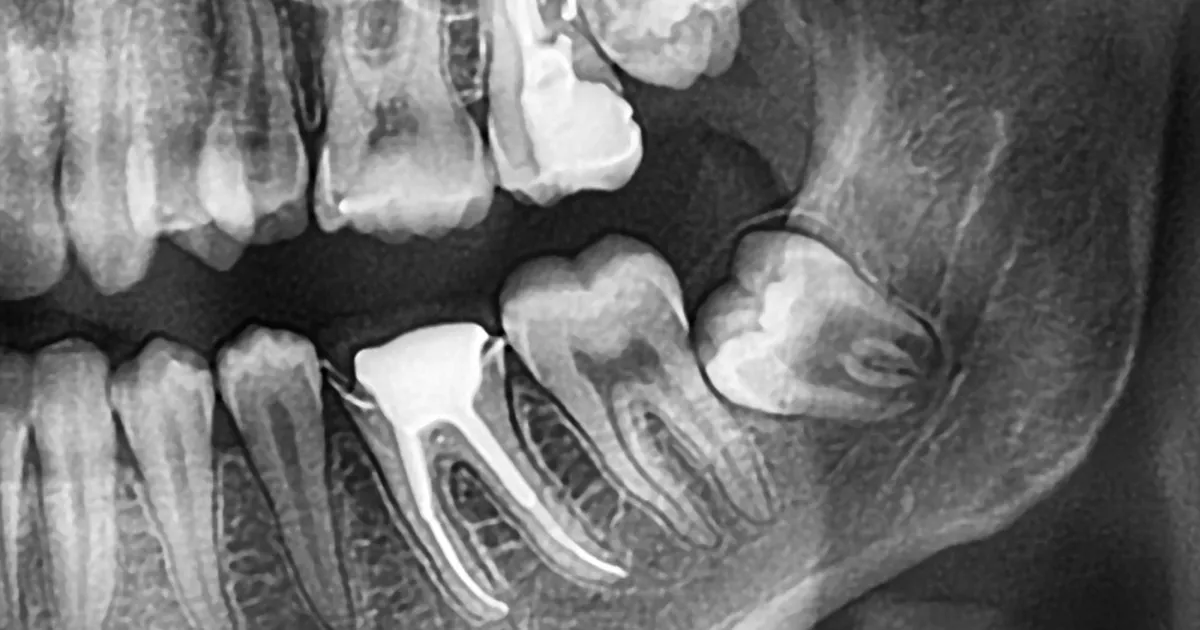

歯科ハミール高田88では、CT撮影や最新の3Dスキャナー「iTero」を導入しており、抜歯前の詳細な診断を行います。

これにより、歯の位置や形状、周囲の骨構造を正確に把握し、リスクを最小限に抑えた安全で確実な治療が可能です。

CTによる立体画像解析により、神経や血管の位置も明確にし、難易度の高い親知らずの抜歯にも対応しています。

この先端技術により、術後の合併症リスクも大幅に低減できます。